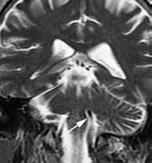

Our case involved a 57-year-old man presenting with weakness of the left face for the previous 18 months with acute worsening over the course of that day. Transient ischemic attack was ruled out, although a vascular loop of the ipsilateral vertebral artery was observed on magnetic resonance angiogram (MRA) of the brain to be impinging on the facial nerve (figure). The patient was treated with muscle relaxants with some relief of the symptoms, and he was discharged to be followed for further evaluation of the symptoms.

Figure. Noncontrast MR examination at the level of the cerebellopontine angle reveals a vascular loop corresponding to the distal portion of the left vertebral artery, compressing the area at the origin of the left facial nerve at the pontomedullary junction (A and B). In the axial (C) and coronal (D) T2W images, the arrows point to the flow void of the vessel. In the axial image of the source angiogram (C) and in the coronal view of the time-of-flight image (D), the arrows identify the vessel to better advantage than in A and B. The thin arrow in panel C identifies the left anterior inferior cerebellar artery.

Visualization of the vascular structure and the nerve is best achieved in oblique sagittal gradient MR imaging, which is reported to have a 75.9% sensitivity for identification of facial nerve compression by the anterior inferior cerebellar artery or the posterior inferior cerebellar artery, the first and second most common offending vessels, respectively.8

Neurovascular compression involving the vertebral artery, which accounts for a minority of cases (17%), can be evaluated with 100% sensitivity due to the vessel’s larger caliber.8,9 MRA and computed tomography angiography have demonstrated similar utility in identification of pathologic vessels.10